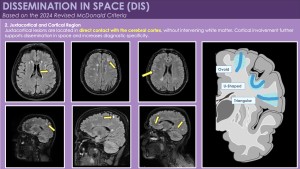

1. Dissemination in Space (DIS): Updated MRI Definition

According to the 2024 McDonald criteria, dissemination in space is demonstrated by typical demyelinating lesions in at least two of five anatomical regions:

- Juxtacortical / Cortical